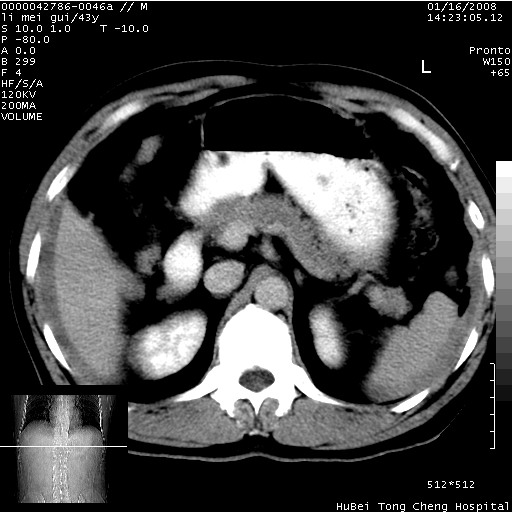

| 患者,男,43岁。突发腹痛2小时,面色苍白,难以平卧。自述近期无明确外伤史,为摩托车驾驶员。 腹部b超检查:脾脏中上极回声异常,肿瘤待排。 临床诊断:腹痛原因待查。 上中腹部ct轴位平扫+增强扫描(层厚10mm,螺距1.0,重建间隔10mm),图像如下: ![]() ![]() ![]() ![]() ![]() ![]() ![]() ![]() ![]() ![]() ![]() ![]() ![]() ![]() ![]() ![]() ![]() ![]() ![]() ![]() ![]() ![]() ![]() ![]() ![]() ![]() ![]() ![]() ![]() ![]() ![]() ![]() ![]() ![]() ![]() zrs发言:支持脾破裂 wwp发言:支持脾破裂并腹水。 xulianj发言:脾脏肿瘤破裂可能性大 zsl6918发言:不像肿瘤出血,考虑还是与外伤后引起的慢性出血有关 zzyy发言:平扫见肝周及脾周积液,脾内密度不均。脾内肿瘤较少见。还是外伤性脾破裂。 沈丘东方医院发言:脾门区一个不均匀强化病灶与其周液体相连多考虑脾占位破裂出血 yixianman001011发言:脾破裂并腹水是可以肯定的,具体原因多以肿瘤性破裂出血,脾脏淋巴瘤可能性大. 结果: 术后,经详细询问患者,其仔细回忆:一月前骑摩托时左侧腰部与别人有“轻微”触碰,因责任在自已,当时又无明显不适,未引起注意。 临床术后诊断:脾破裂并失血性休克(1.外伤性迟发性脾破裂。2.脾脏肿瘤破裂?) 术后标本病检:脾破裂并出血,未见明显肿瘤成份。 原贴地址:http://www.radinet.com.cn/forum_view.asp?forum_id=4&view_id=34070 |